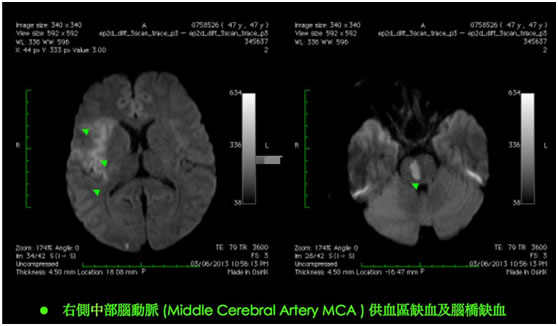

HKBSSP 推出治療急性缺血性中風的嶄新「黃金八小時」概念: 腦內血管介入的微創手術(機械式吸取血栓術),正正填補了靜脈注入溶血劑rtPA的黃金3至4.5小時治療方案的不足。 病人可於中風症狀出現後的八小時內接受腦內血管介入的微創手術(機械式吸取血栓術),把血管再次灌通。就像心臟的通波仔微創手術, 專攻腦內血管治療的神經外科醫生會從腹股溝把微型導管放入腦血管,擊碎及吸走腦內血栓,把血管再次灌通, 令腦細胞重獲生機。腦內血管微創手術在大腦血管造影導引下,不但能於大腦栓塞的確實位置進行治療,高度準確地移除血栓。 有時候,如果神經外科醫生發港現病變和狹窄的腦動脈, 而其是造成中風的主要原因,醫生植入柔軟的金屬支架, 將大腦動脈重建。